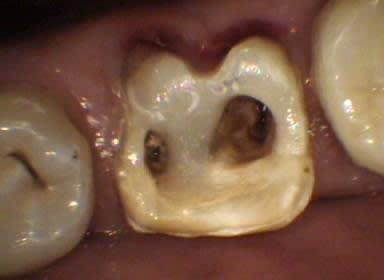

Ceci est un exemple de traitement de poches par photo-ablation en une seule séance en mode continu sans contact, cette technique diffère des traitements par lasers fibrés.

Après sondage et traitement médical, la gencive non attachée est volatilisée avec stérilisation et hémostase immédiate. La cicatrisation est rapide et la ré-attache se réalise en quelques jours, laissant dégagés les espaces biologiques afin de permettre un entretien aisé par le patient, la texture de la gencive prenant un aspect en peau d'orange et reformant progressivement un feston.

Marc, évidemment qu'il s'agit de gingivectomie, je dirais même plutôt gingivoplastie, la gencive est sculptée par le laser plus fidèlement qu'avec un bistouri ou une fraise car il suit exactement le trajet et la profondeur de chaque poche sans sectionner à l'emporte pièce.

J'ai rajouté les photos vestibulaires sur mon premier post, les poches étant un peu moins profondes qu'en palatin.

La différence ne s’arrête pas seulement là, car comme te l'a très bien expliqué Emma, le laser représente bien plus qu'un simple instrument de coupe ou de nettoyage, aucun bistouri ni aucune curette n'est capable de stériliser, d'assurer l'hémostase immédiate, d'activer la cicatrisation ou encore de pratiquer une suture avec un confort pour le patient nettement amélioré. Tu pourrais à la rigueur le comparer à un bistouri électrique mais celui-ci n'a qu'un effet de surface limité.